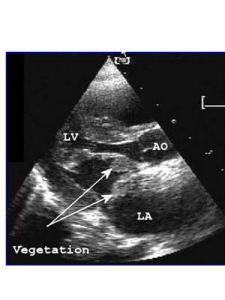

1.發病機制血流動力學改變造成的內皮損傷和菌血症的發生,是形成感染性心內膜炎最重要的機制,在正常情況下,如有少數病原體由口腔,鼻,咽部以及皮膚等部位進入血流後即被迅速消滅,當有器質性心血管病變時,病原體可在受損的心瓣膜,心內膜或血管內膜棲居,周圍有附著的血小板血栓及紅細胞和白細胞,並被纖維素所包裹而形成贅生物,形成心內膜炎症,心臟結構異常(如瓣膜狹窄或關閉不全,心內分流)引起的血流動力學改變是內皮損傷的基礎,機制為:高速噴射性血流衝擊內膜;瓣膜口狹窄形成壓力階差,大多數情況下內皮損傷發生在壓力階差的低壓側,菌血症的發生常由侵入性醫療操作引起,如牙周病手術後菌血症的發生率高達88%,內皮損傷後血小板與纖維蛋白聚集在損傷處,形成無菌性贅生物,如有菌血症發生,則形成感染性贅生物,贅生物一旦形成,在血流的持續衝擊下,將導致贅生物破碎和體內器官的栓塞。

(1)心臟及血管:本病的基本病理改變是心瓣膜,心內膜及大血管內膜表面附著疣狀感染性贅生物,活動期贅生物分3層:最裡層主要由血小板,纖維素,紅細胞,膠原纖維,壞死組織及細菌組成;中層由細菌組成;外層由纖維素與細菌組成,癒合期最外層被纖維素所覆蓋,中層及內層發生玻璃樣變與鈣化,心瓣膜的贅生物可造成瓣膜潰瘍及穿孔等,還可累及腱索及乳頭肌,使腱索縮短或斷裂,動脈瘤,巨大的贅生物可堵塞瓣膜口,導致急性循環障礙,贅生物受血流衝擊常有細微栓子脫落,由於栓子的大小及栓塞部位的不同,可發生不同的器官栓塞症狀並引起不同的後果,左心脫落的栓子引起腎,腦,脾,肢體和腸系膜動脈栓塞;右室的栓子引起肺栓塞,其中肺栓塞的發生率最高,微小栓子栓塞毛細血管產生皮膚瘀點,在小動脈引起內皮細胞增生及血管周圍炎症反應,形成皮膚的歐氏小結(Oslersnodes),感染性栓子栓塞後可發生以下變化: